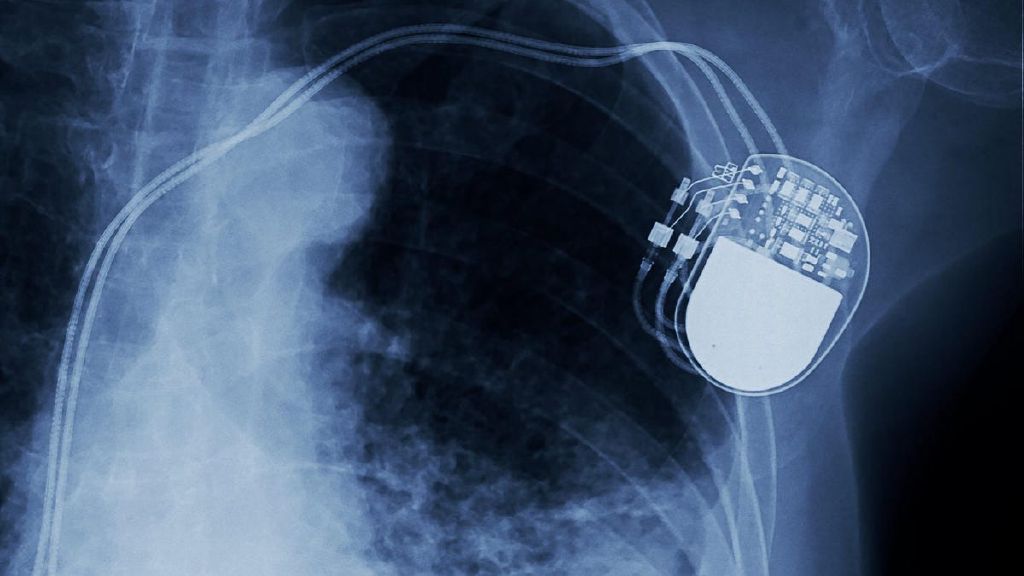

12 Real Body Modifications, Ranked by Their Usefulness

If you're hoping to transcend your humanity through technology, consider these 12 tech-implants.